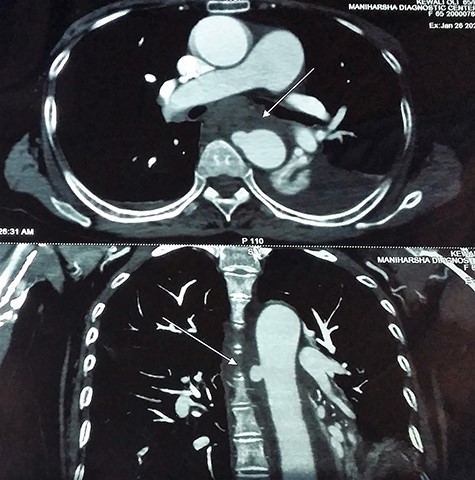

With the above findings, a diagnosis of ruptured descending thoracic aortic aneurysm with AEF was made. The patient was immediately taken for emergency TEVAR where 34 × 34 × 167-mm stent graft (Medtronic Inc. Valiant Thoracic Stent Graft) was deployed using a guidewire beyond the left subclavian artery till above the diaphragm via an incision over the left common femoral artery. Check angiogram showed no leak (Figs 4 and 5). Due to existing mediastinitis, feeding jejunostomy (FJ) was preferred over esophageal stenting. FJ was performed in the same setting after the endovascular procedure.

After 6 weeks, when mediastinitis subsided, gastrograffin swallow was done, which showed no esophageal leak suggesting spontaneous healing of perforation (Fig. 6). Oral feed was commenced with liquid and, subsequently, a normal diet.